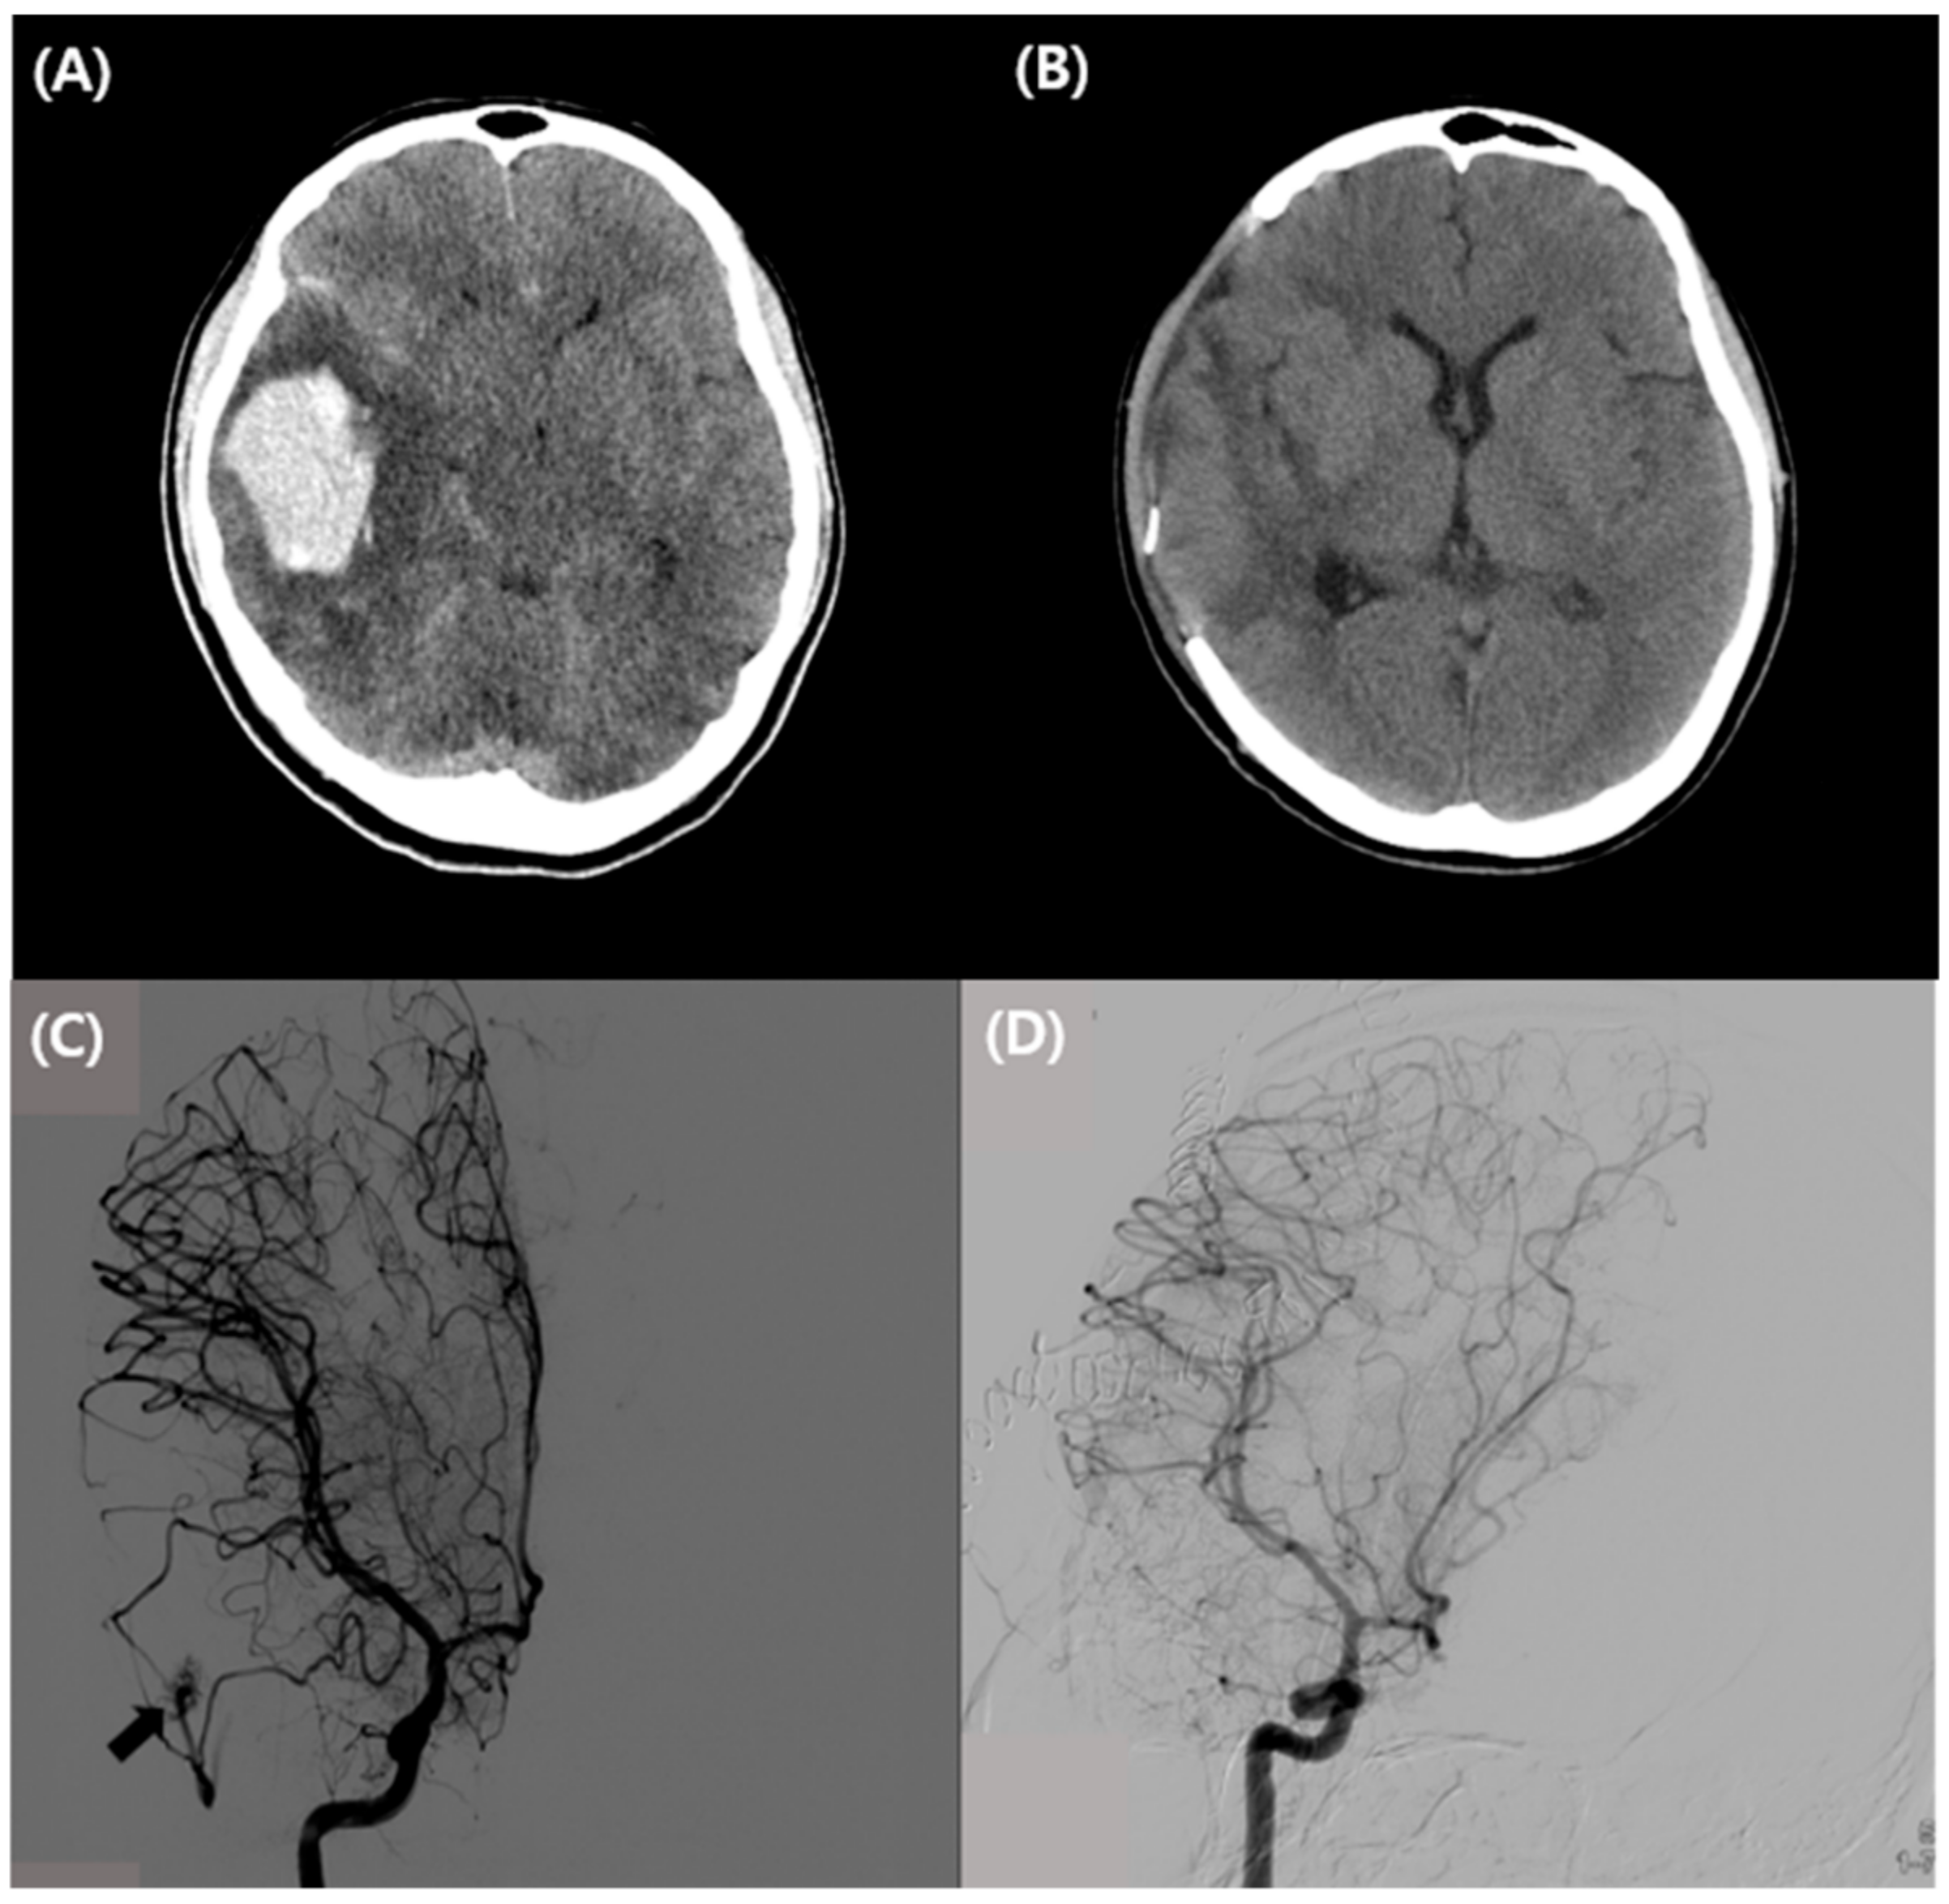

2. Case Presentation